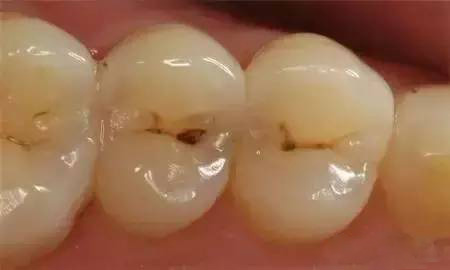

浅龋早期龋齿仅波及牙釉质,在釉质的表面出现大小不一的黄褐色斑点,一般无症状,常常不易被察觉,大多数患者在口腔检查时才发现。这一期的龋齿成为浅龋。中龋当龋坏进一步发展,波及牙本质浅层时,称为中龋。此时龋病进展快,易形成龋洞,呈黄褐色或深褐色。患者可有临床症状,常常表现为酸甜饮食或过冷过热饮食时牙齿感到酸痛,刺激去除后酸痛感立即消失;也有部分患者没有临床症状。